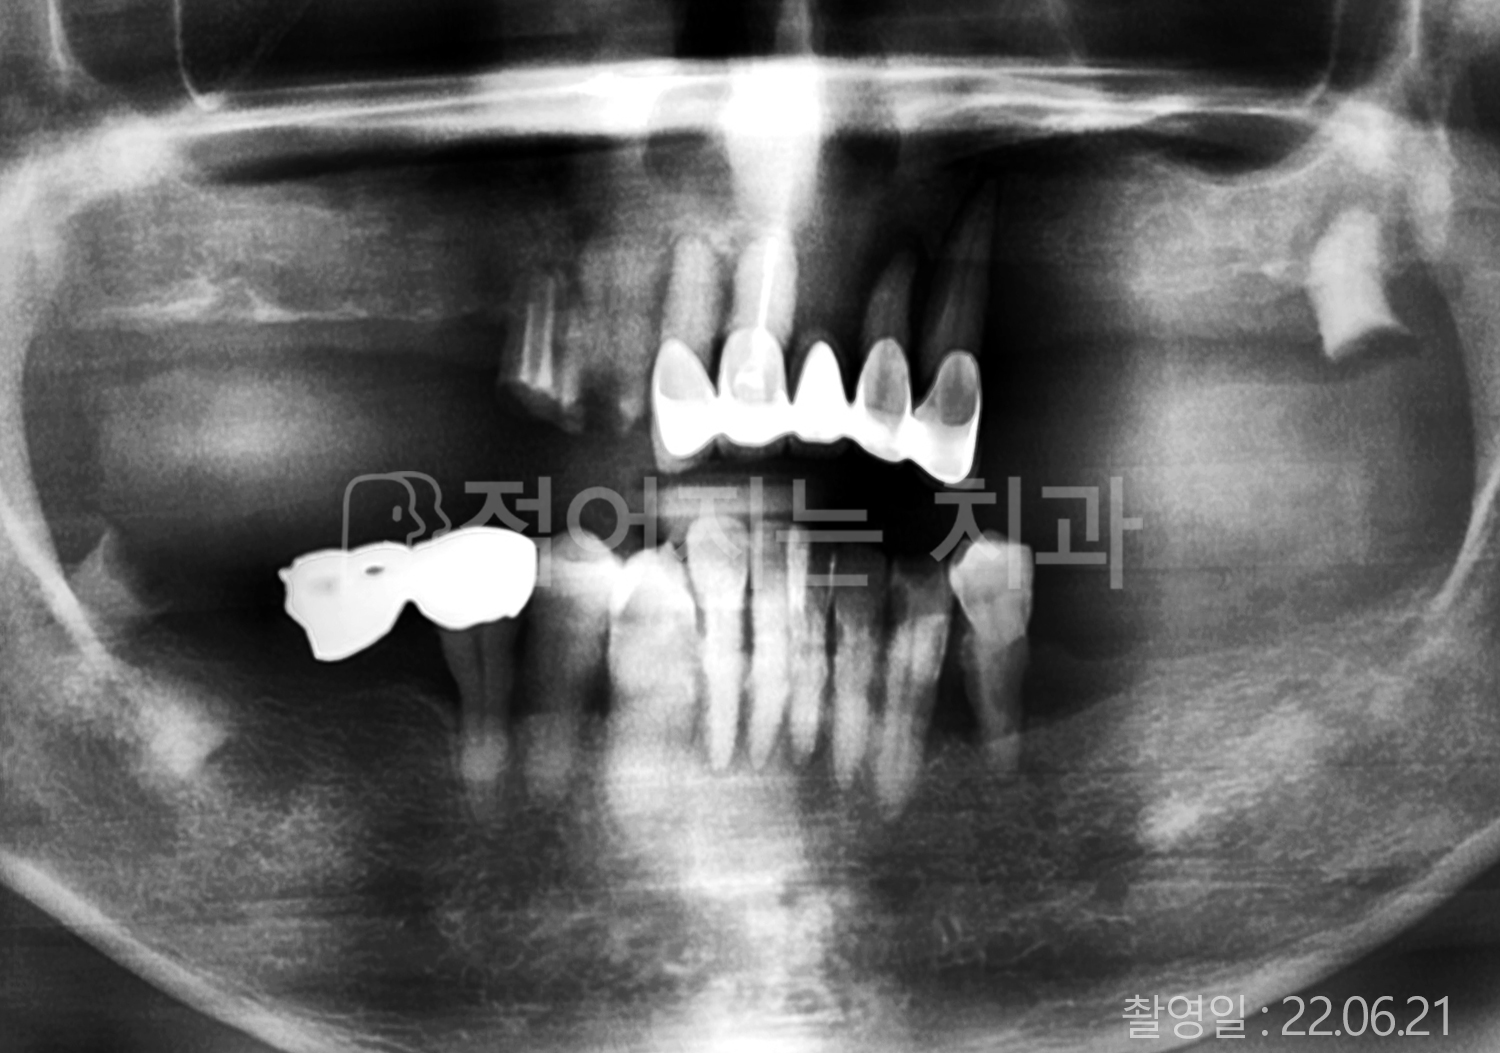

• 50대 전체치아 10개 이상 임플란트